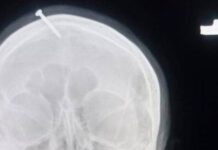

Mulher descobre pano dentro do ânus depois de dois meses de cesárea

Brasil- Uma mulher teve uma infecção no reto, após descobrir que tinha um pano que foi deixado no ânus após uma cesárea ocorrida no...